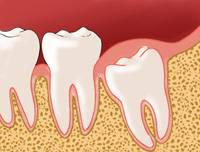

Alors pourquoi s’en prend t-on aux dents de sagesse ? Si elles existent c’est bien qu’elles doivent servir à quelque chose n’est-ce pas ? Effectivement mais bien des dentistes décident de les faire enlever à leurs patients pour anticiper un problème : infection lors de la pousse, déplacement des autres dents etc… Il arrive en effet que les dents de sagesse n’aient plus beaucoup de place pour pousser et qu’elles soient obligées de pousser les dents déjà en place. Ces troisièmes molaires sont donc enlevées de manière quasi systématique car ces opérations sont un business très lucratif !